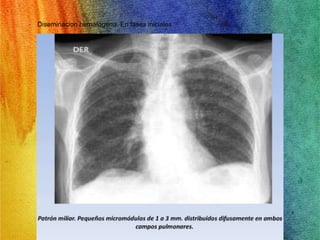

• Diseminacion hematogena. En fases iniciales

TUBERCULOSIS MILIAR

• Consiste en una siembra hematógena de bacilos tuberculosos. En

los niños suele deberse a una infección primaria reciente, pero en

los adultos puede ser secundaria tanto a una infección reciente

como a la reactivación de focos diseminados antiguos

Las lesiones son granulomas

pequeños (1-2 mm) y los

sintomas son inespecificos.

Hepatomegalia,esplenomegalia,

linfadenopatia, tuberculos

coroideos en el ojo.

• 64.

• Diseminacion hematogena.En fases iniciales